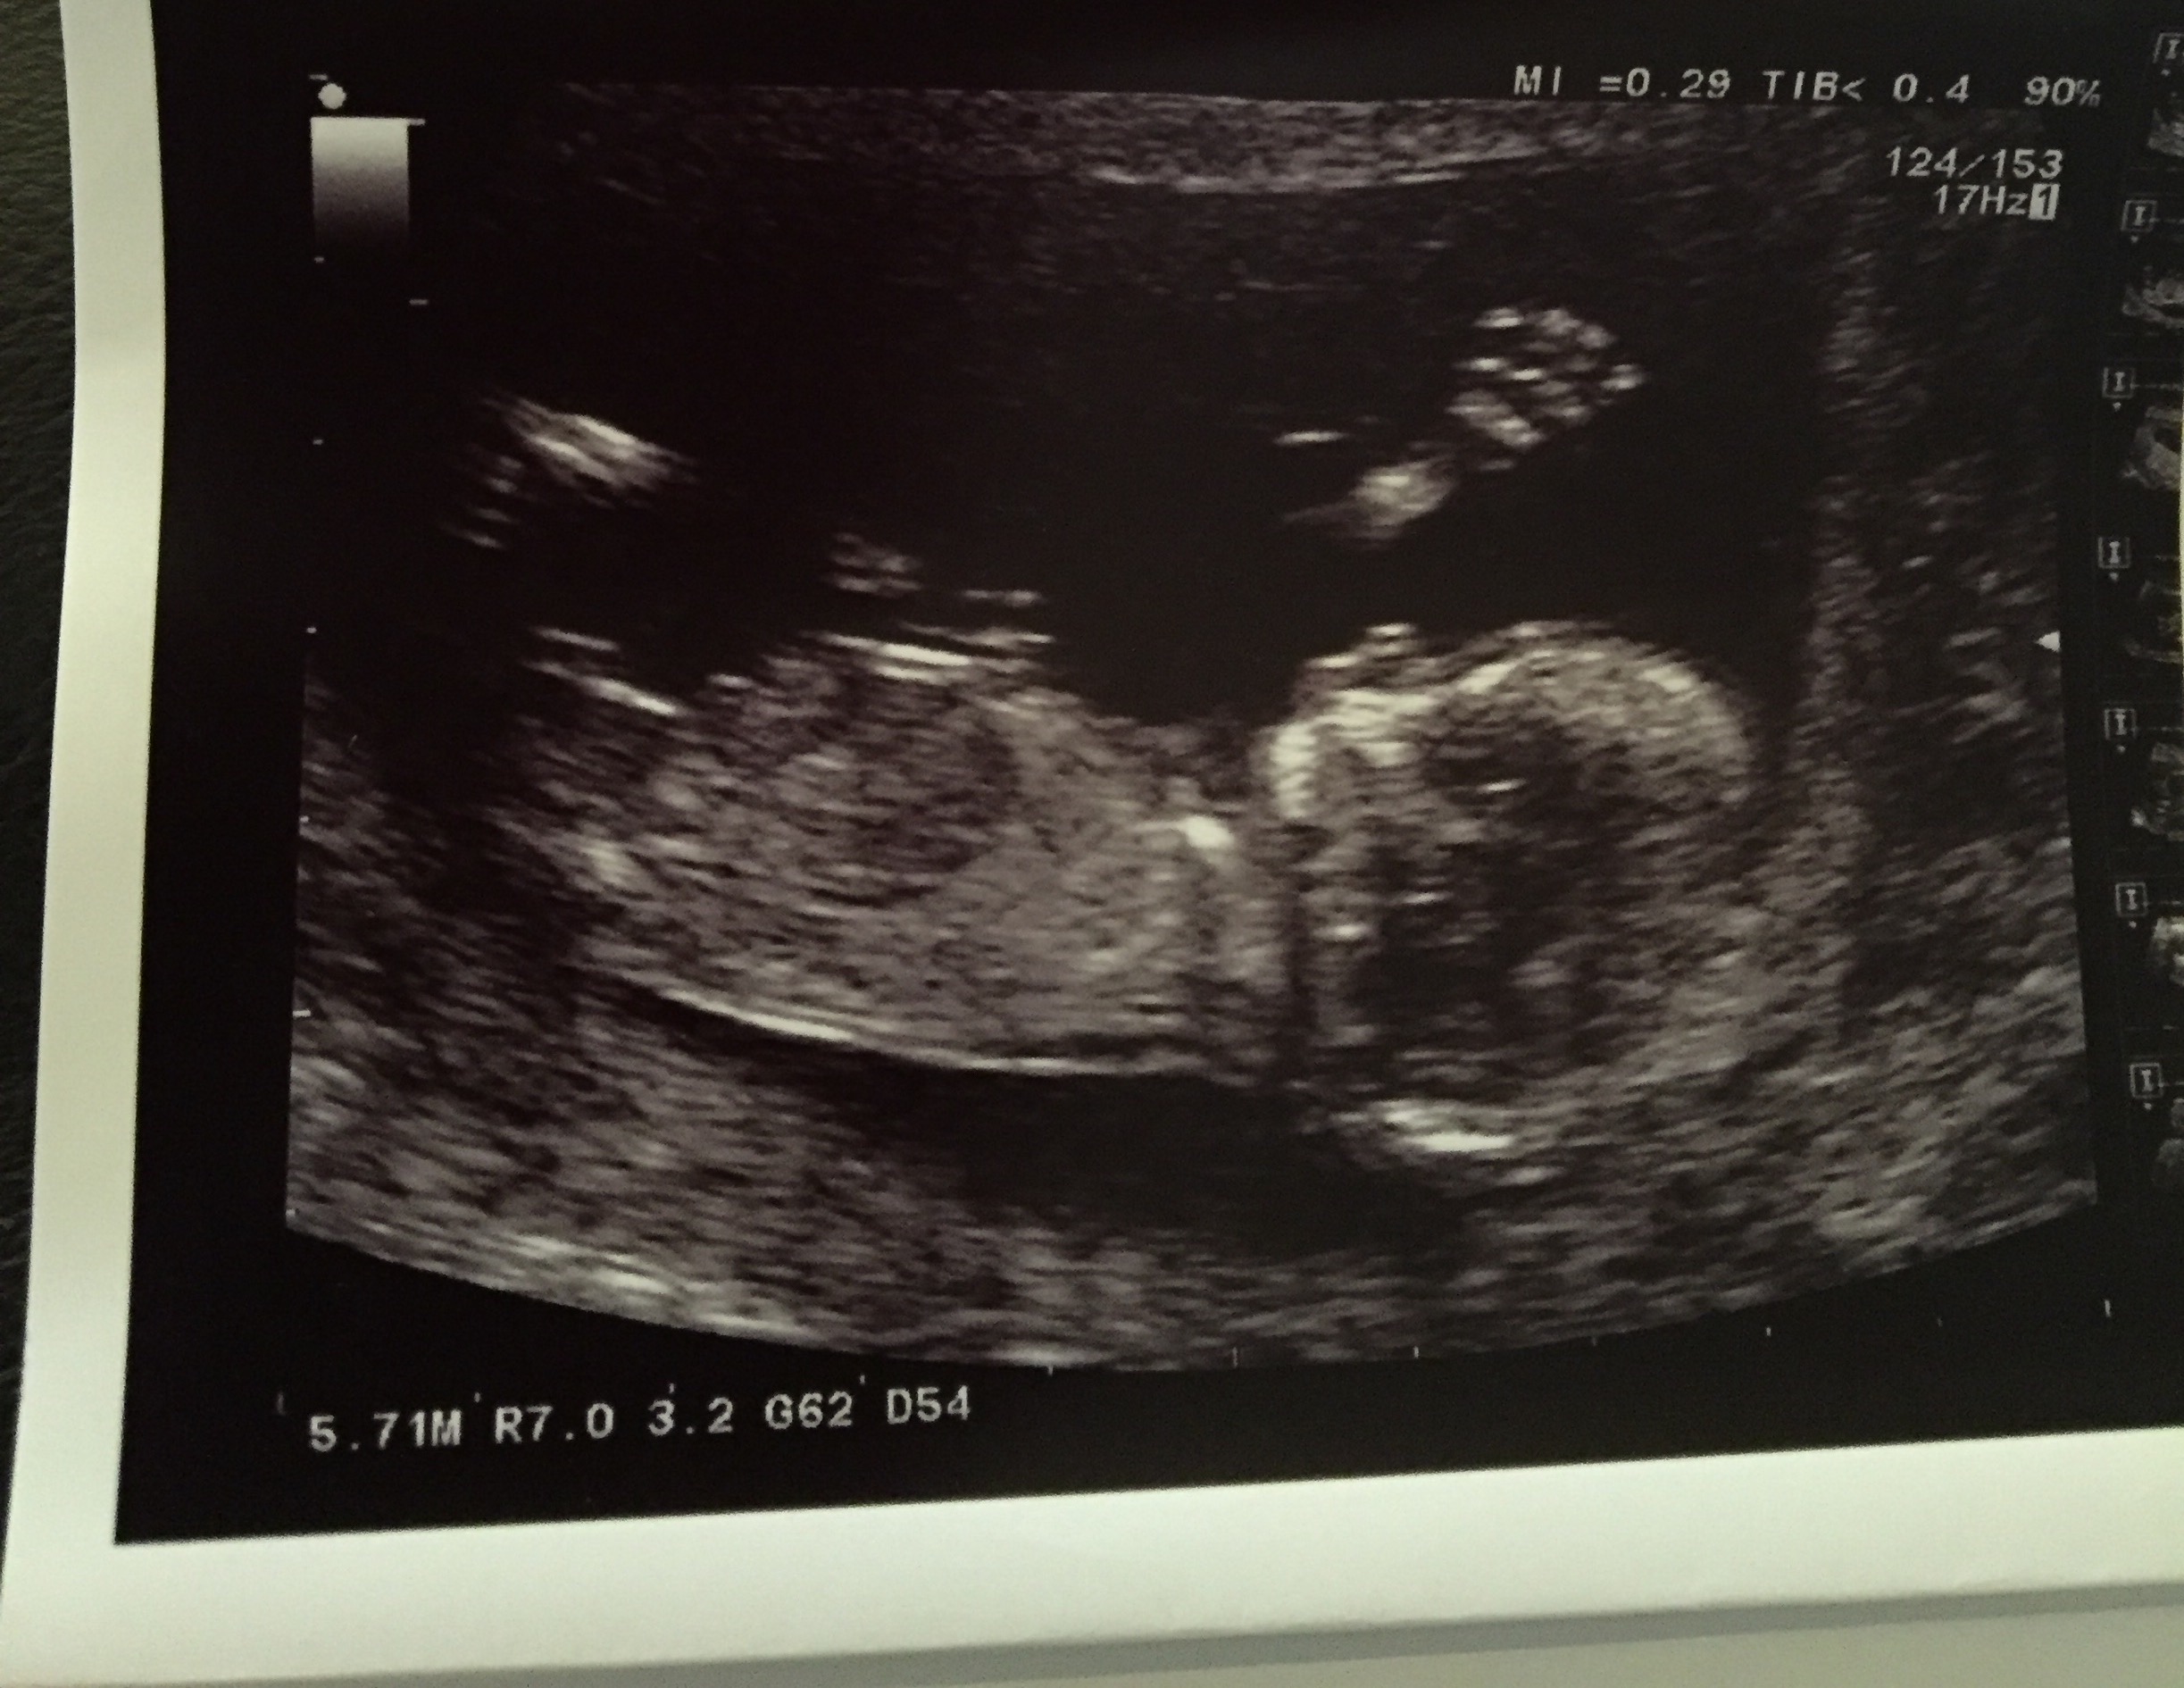

Maybe boy

Thinking girl

Boy nub, I am seeing stacking on the end of the nub Were you hopying for a certain gender??

I agree with dreaming, boy.

I think its a girl.